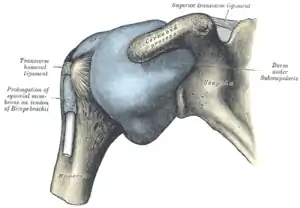

Capsule of shoulder-joint (distended). Anterior aspect. | |

The capsule is a soft tissue envelope that encircles the glenohumeral joint and attaches to the scapula, humerus, and head of the biceps. It is lined by a thin, smooth synovial membrane. This capsule is strengthened by the coracohumeral ligament which attaches the coracoid process of the scapula to the greater tubercle of the humerus. There are also three other ligaments attaching the lesser tubercle of the humerus to lateral scapula and are collectively called the glenohumeral ligaments.

The transverse humeral ligament, which passes from the lesser tubercle to the greater tubercle of humerus, covers the intertubercular groove, in which the long head of biceps brachii travels.